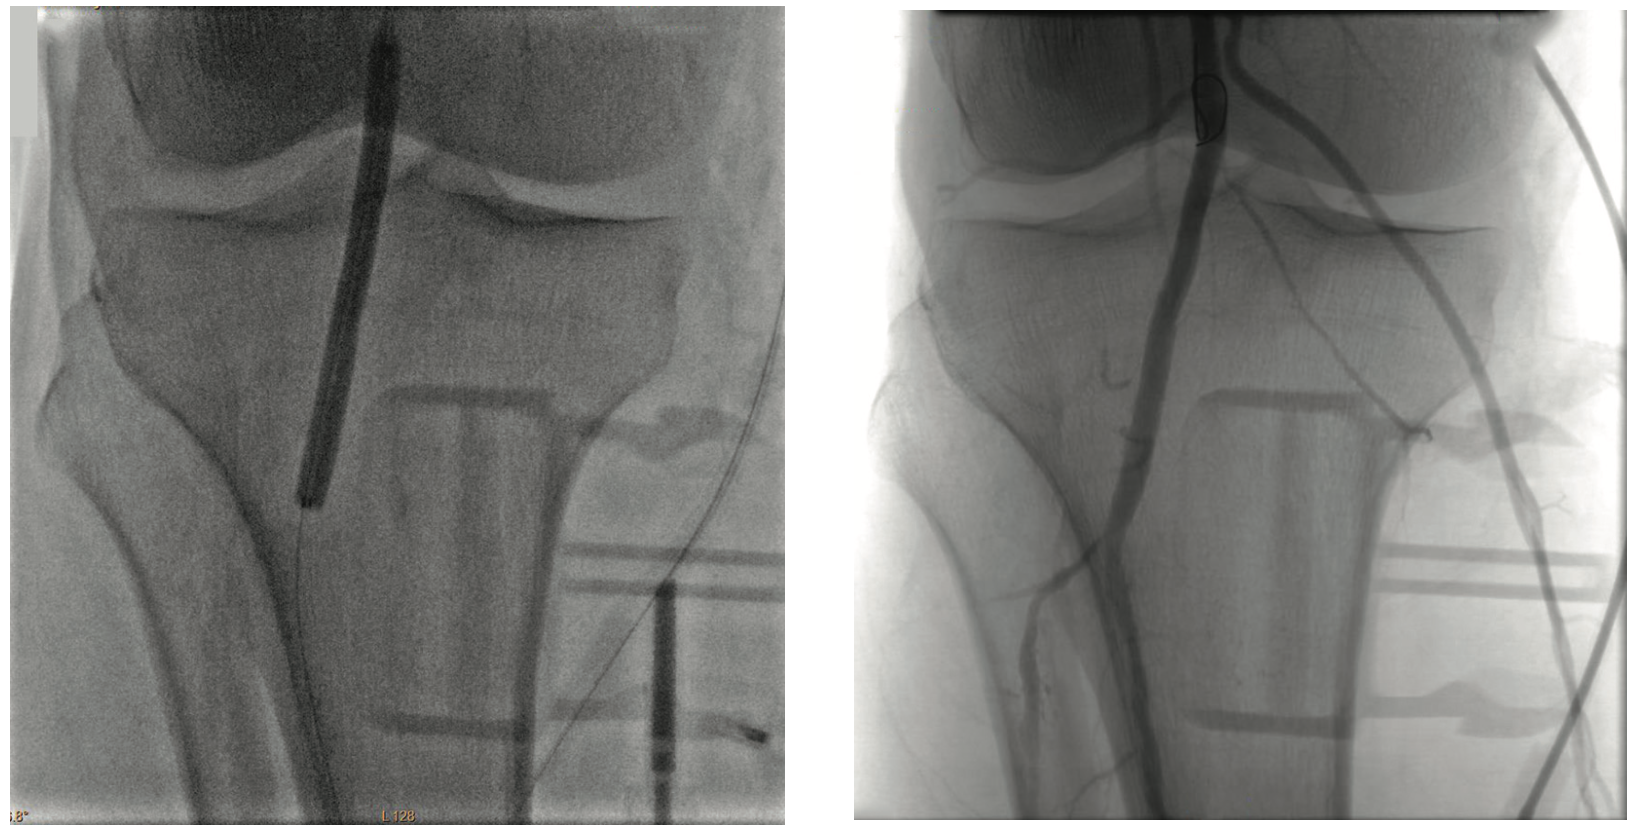

Inflow in the popliteal was optimized with plain balloon angioplasty (POBA) prior to addressing the BTK lesions (Figure 2). A 3 mm x 120 mm Serranator PTA Serration Balloon Catheter (Cagent Vascular) was utilized with serial overlapping inflations to treat the anterior tibial artery. The Serranator was used distal to proximal with max inflation at 12 atmospheres (atm) for two minutes (Figures 3-4). A 3 mm x 80 mm Serranator balloon was then used in a similar manner to treat the TPT, with a maximum inflation of 8 atm for two minutes. Following Serranator use, significant lumen gain and improved flow was observed, with 0% stenosis and no dissection, perforation, or recoil noted (Figure 5).